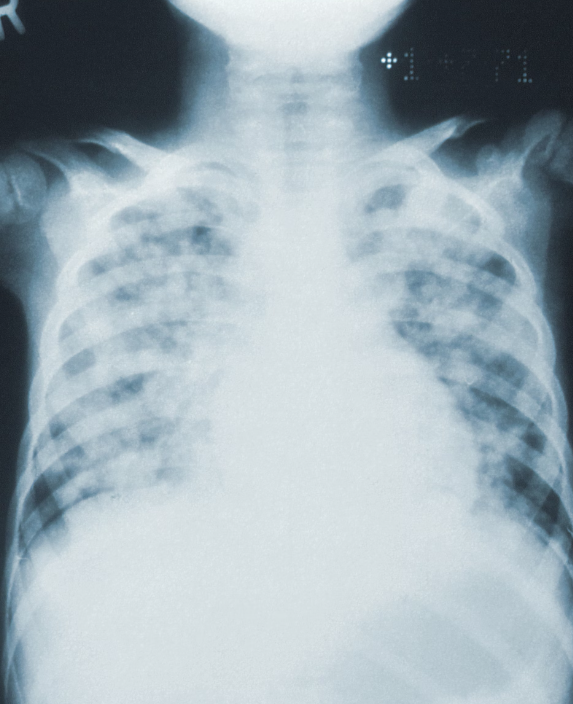

폐렴은 흔하지만 심각할 수 있는 호흡기 질환입니다. 특히 면역체계가 약하거나 만성 질환을 가진 사람들에게 위험할 수 있습니다. 이번 포스팅에서는 폐렴이 무엇인지, 그리고 그 증상을 자세히 알아볼 것입니다. 정확한 지식은 폐렴을 조기에 발견하고 적절한 치료를 받는 데 도움이 됩니다. 그러니 조심스럽게 살펴보고, 여러분의 건강을 위한 필요한 정보를 얻으시기 바랍니다.